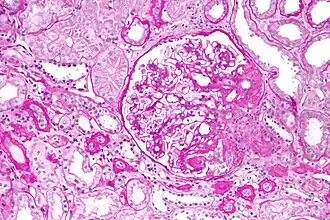

![]() Micrografía óptica de una Glomeruloesclerosis focal y segmentaria, variante hiliar. Biopsia renal. Tinción de PAS. | ||

Los componentes individuales del nombre de esta enfermedad se refieren a la apariencia del tejido renal en la inspección de una biopsia: es focal porque solo algunos glomérulos se ven afectados—lo opuesto es difusa—, segmentaria significa que solo una parte del glomérulo está afectada—lo opuesto es global—y glomeruloesclerosis se refiere a la cicatrización del glomérulo, la porción funcional de la nefrona.